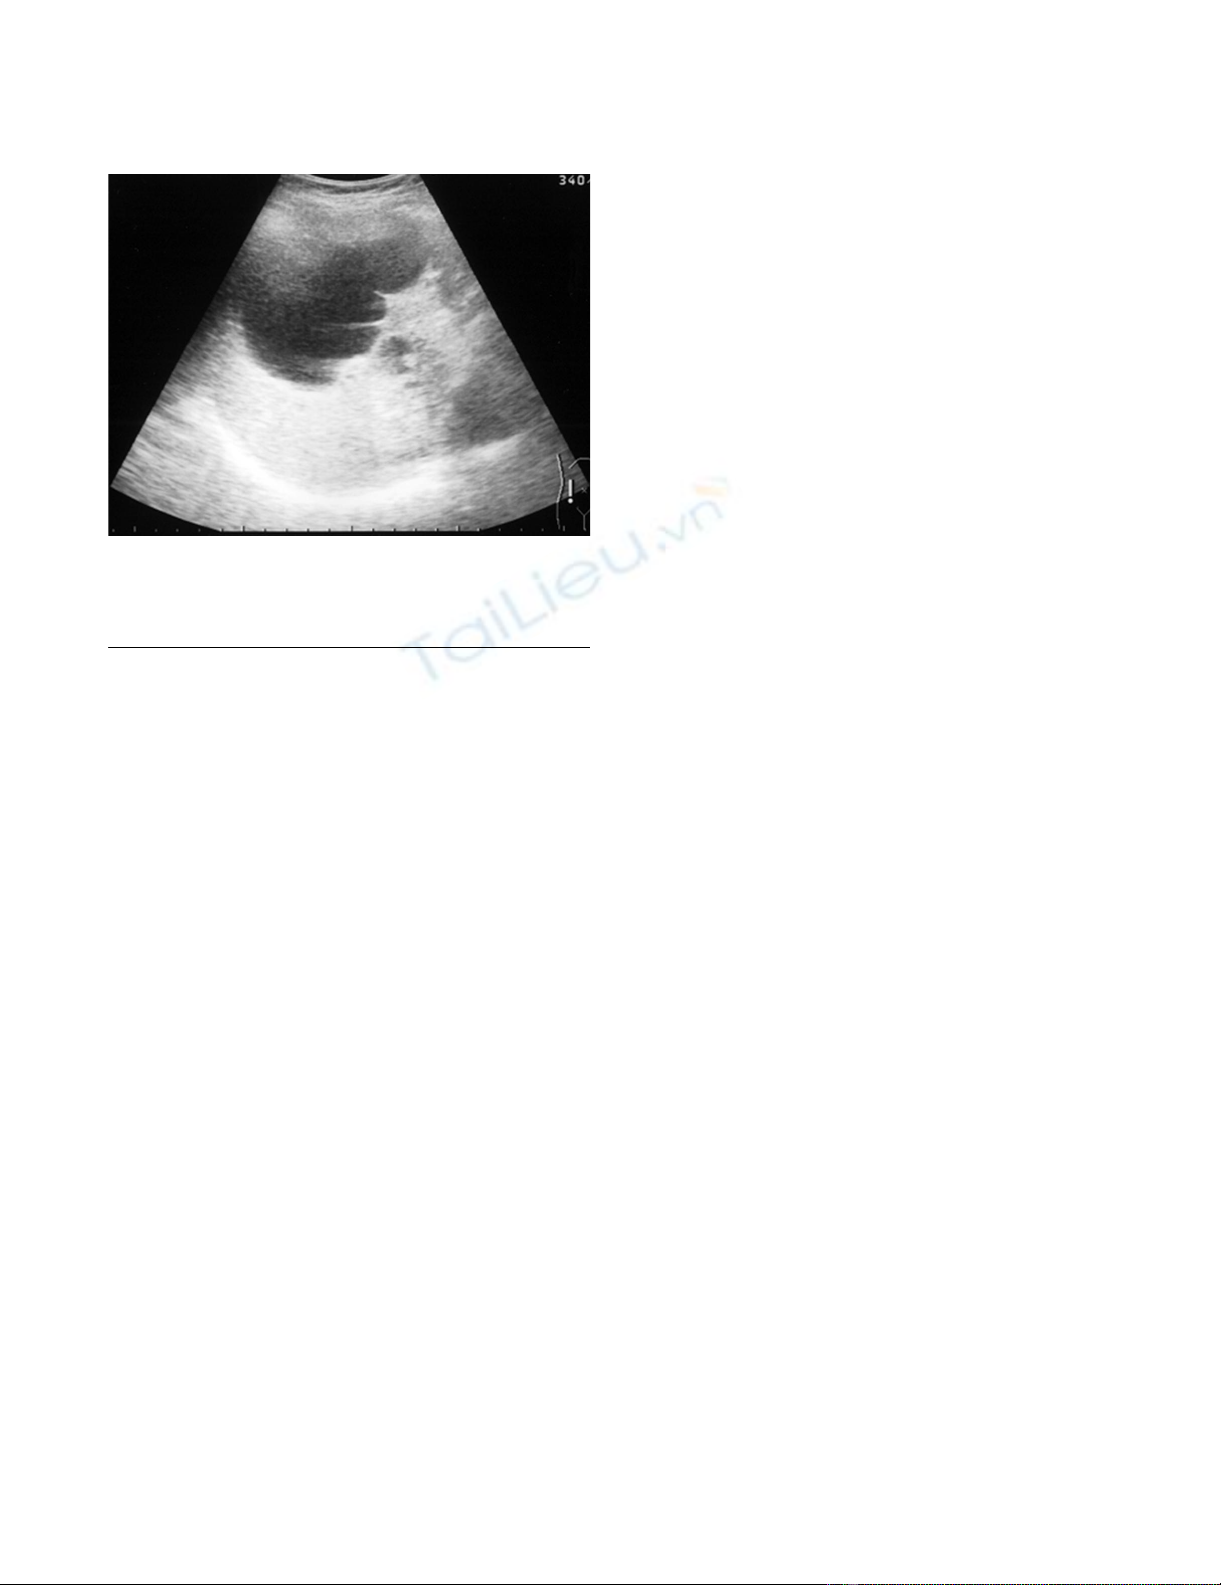

high intensity T2-weighted image (Fig. 3a, b). US revealed

a unilocular cyst over 10 cm in diameter and partial septa

within the cyst (Fig. 4). Abdominal angiography showed

Abdominal US in 2004, showing the unilocular cyst over 10 cm in diameterFigure 4

Abdominal US in 2004, showing the unilocular cyst

over 10 cm in diameter. Partially, the septa within the

cyst were seen.